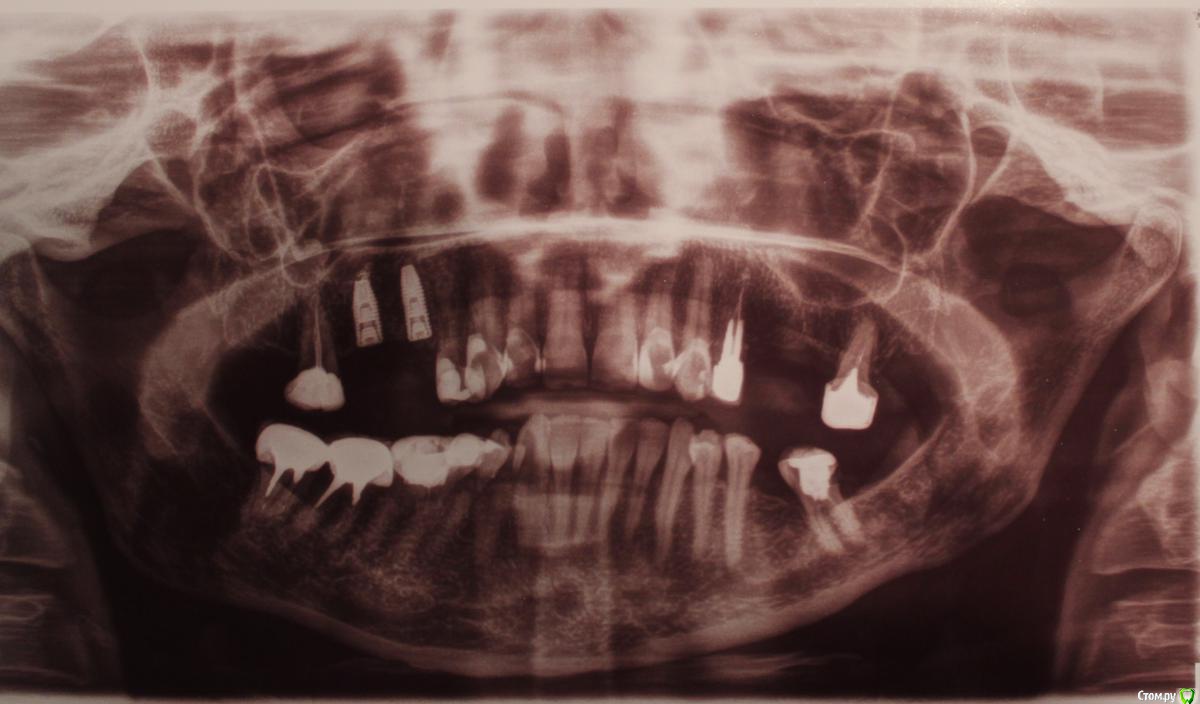

Patient_Nobel Опубликовано 27 июля, 2019 Поделиться Опубликовано 27 июля, 2019 (изменено) Здравствуйте, уважаемые форумчане! Поставили импланты , рядом с ними остался один зуб. Если по снимку смотреть - верхний левый крайний. Семерка ( по современному не знаю названия).До установки имплантов врач ничего о нём не говорил. А после установки сказал, что им нужно заниматься до установки коронок на импланты и для этого лучше посмотреть под микроскопом, в чем там проблема. Хотя они же мне делали КТ. Разве в разрезах КТ не видно всех проблем?Возможно, нужно будет ставить на него коронку.Что посоветуете? Действительно ли там что-то серьёзно нужно делать? Сейчас он меня совершенно не беспокоит. Изменено 27 июля, 2019 пользователем Patient_Nobel Ссылка на комментарий

St. Опубликовано 27 июля, 2019 Поделиться Опубликовано 27 июля, 2019 Добрый день. Да, все логично. На зубе сейчас масивная пломба, чтобы хорошо восстановить форму зубов на имплантах и плотность контакта между зубами и новыми коронками логично покрыть 7 зуб коронкой. Перед этим проверяют как лечены каналы (насколько плотно и т.д.) под микроскопом это делать удобнее, и по необходимости перелечивают. Ссылка на комментарий

red_butler Опубликовано 31 июля, 2019 Поделиться Опубликовано 31 июля, 2019 И ещё мне не понятно - этот зуб обязательно нужно лечить? для отвела нужна Кт Там какие-то проблемы сейчас видны? большая степень разрушения Ссылка на комментарий